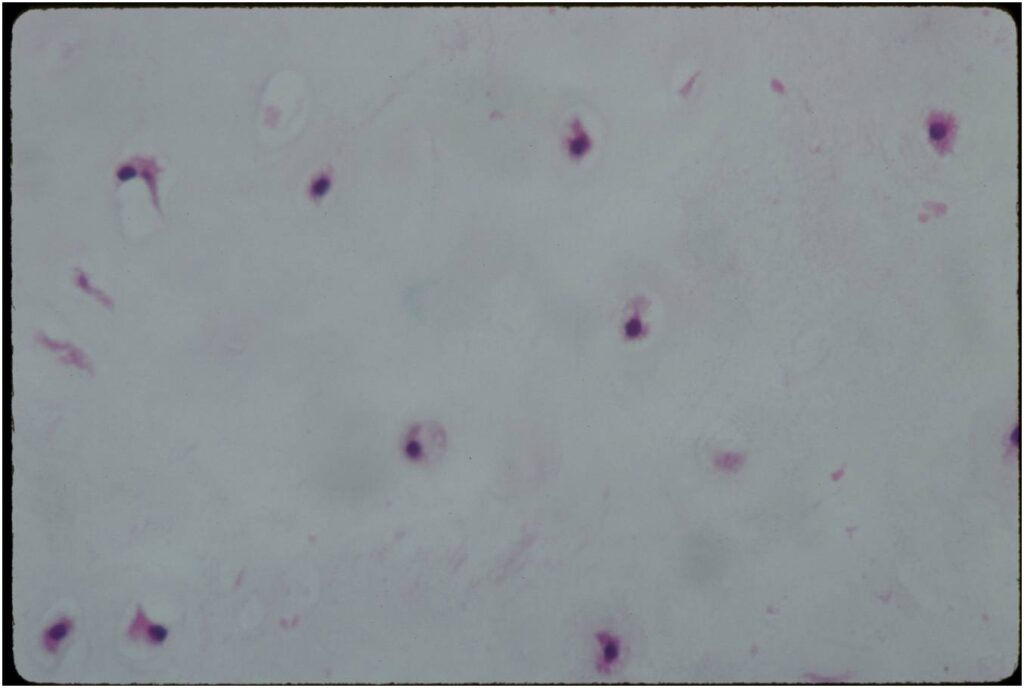

Microscopic Pathology

- Enchondromas are well defined lesions with cartilage arranged in lobules that are separated by fibrovascular septa

- Cells are in lacunae and have small dark nuclei

- Low cell count, cells appear bland with few chondrocytes and are similar size and shape

- Although some enchondromas may have areas that are hypercellular and may have two or three cells within a lacunae

- No entrapment or destruction of trabeculae

- There should be no myxoid change in long bone lesions (there is occasional myxoid change in enchondromas of the digits)

- Presence of myxoid change is sign of malignancy